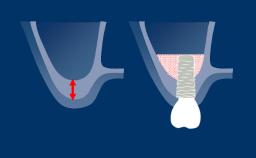

A incisão relaxante periosteal, ou IRP, é uma técnica cirúrgica oral comum realizada para aumentar a mobilidade de um retalho cirúrgico. Quando realizada corretamente, a incisão relaxante periosteal permite que o retalho seja avançado coronariamente para que o fechamento primário sem tensão da região da cirurgia seja possível.